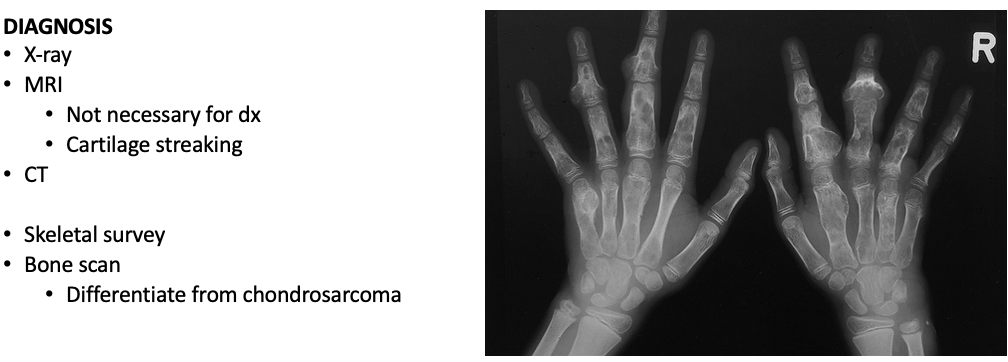

___________ are tumors that effect the cartilage inside the bones

MC benign bone neoplasm of the hand, but can effect other areas

Enchondroma – Benign Bone Tumor

Typically asymptomatic unless accompanied with injury such as a fracture

Symptoms

Pain

Changes in growth

Abnormal exam

Affected area may enlarge

Clinical history/physical examEnchondroma

Bone infarct

Chondrosarcoma

Differential diagnosisEnchondroma

Core needle bx

From areas of bone scalloping or lysis

Histology

Blue-gray lobulated hyaline cartilage with scattered calcifications

WorkupEnchondroma